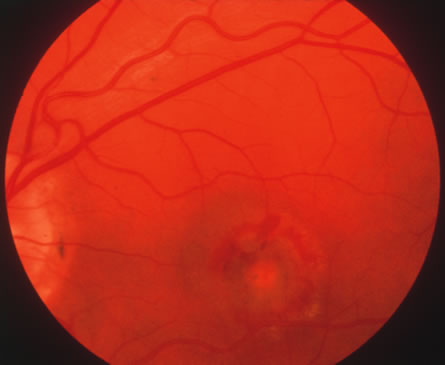

The acute retinal necrosis (ARN) syndrome is most often caused by the herpes zoster virus, although occasionally it may be a result of herpes simplex infection.12 It is typically described in healthy patients although association with immunosuppressed patients has also been described. Granular, nonhemorrhagic areas of retinal necrosis may be observed in the fundus, often rapidly coalescing with resulting blindness often caused by retinal detachment. There is often an associated vasculitis and vitritis. In immunocompromised patients VZV or HSV retinitis may also take the pattern of progressive outer retinal necrosis (PORN) (Fig. 6). PORN differs from ARN in that the former is multifocal, localized to the outer retina, and is less often associated with vasculitis and vitritis.

Fig. 6. Fundus lesions of progressive outer retinal necrosis (PORN). Note the multifocal lesions.